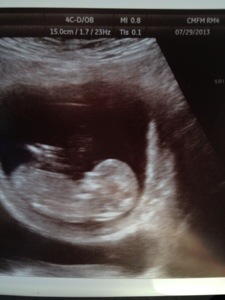

I’m excited for this next journey and all that comes with it. And I’m even more excited to share it with all of you! Say hello to our little miracle! 13 weeks today and doing well. Just perfect! CHEERS to all of you and thank you for sticking with me and always lifting me up! I wouldn’t be here without you all! Xoxoxoxo